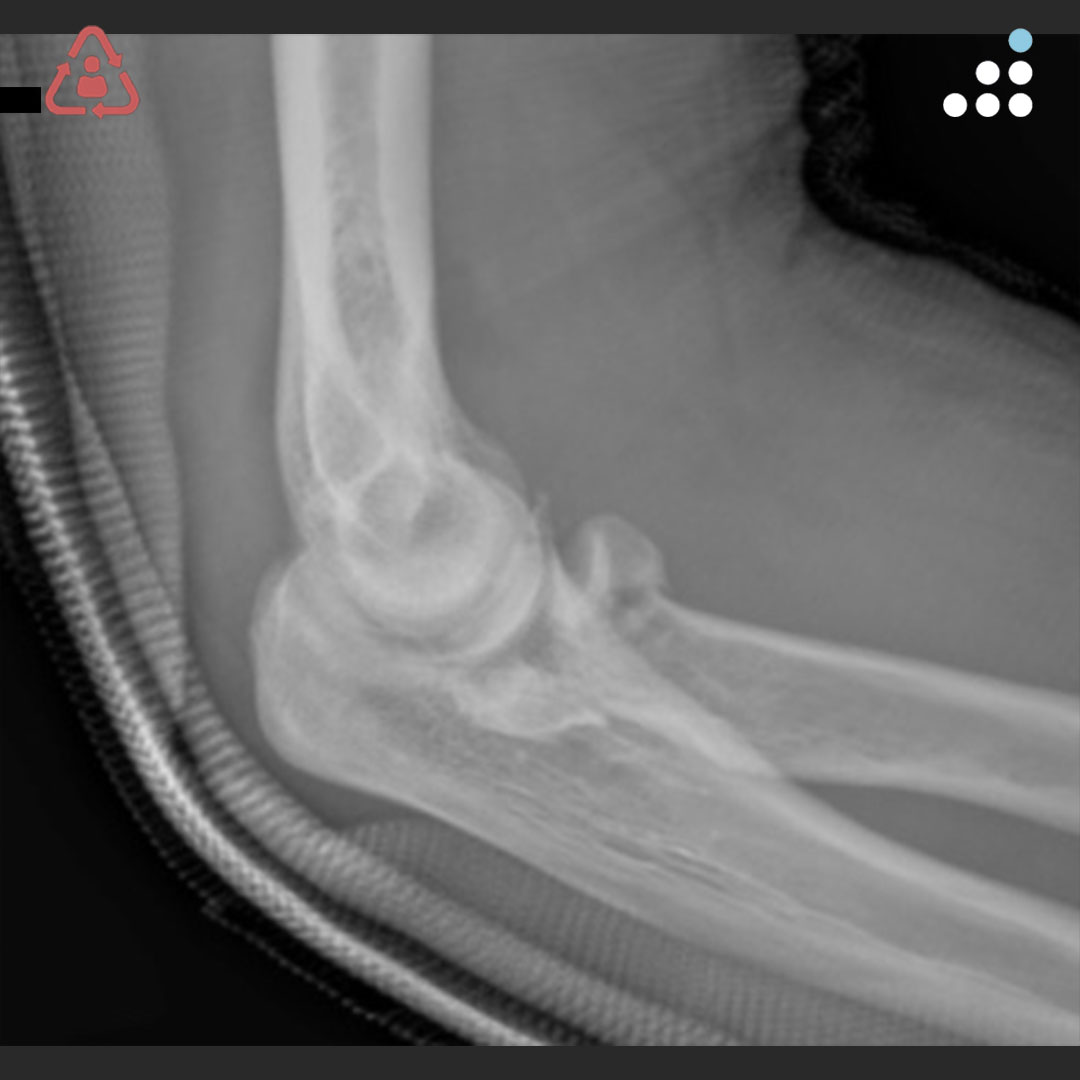

@orthobullets @KPSCALnews @rkh_md @DrMarecek @DeformityDoc @jamesablairMD @FractureDoc @stevemchale @traumaticum @DrFraneNicholas I am concerned about the +Fleck/flake sign. Get MRI or ultrasound to rule out a triceps rupture. If torn, I would perform ORIF and Triceps repair, after restoring the underlying metabolic issues. If the triceps is not torn, then would treat non-operatively.